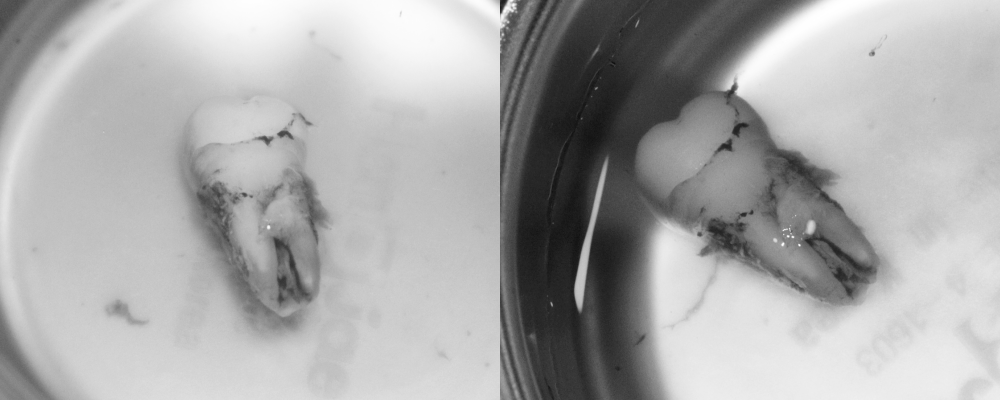

먼저 자연치를 손상시키지 않도록

조심스럽게 발치했습니다.

발치된 상태로 구강 외에서

정밀하게 검사하면서

염증 조직을 제거하는데요.

관찰 결과, 자연치의 형태가 C형으로

특수한 구조를 가지고 있습니다.

이 오목한 부위에 염증조직이

단단하게 달라붙어 있는 것을

확인할 수 있습니다.

이 부분이 바로 신경치료로도

제거되지 않았던 감염 부위인데요.

치근단 부위를 2~3mm 절단한 후

감염된 조직과 오염된 상아질을 제거합니다.

특히 C형 구조의 오목한 부분에

숨어있던 염증조직을

제거하는 것이 치료의 핵심인데요.